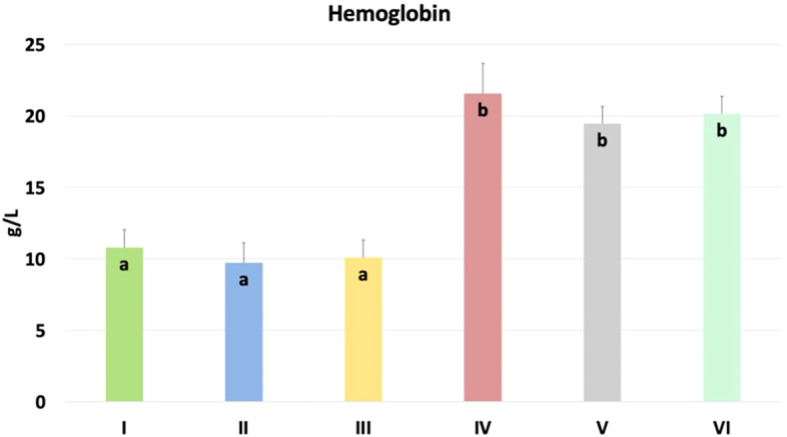

Cannabidiol and nano-selenium affect hemoglobin content in chicken blood

The results of the hemoglobin content in chicken blood are shown in f10. Significantly higher content was found in nano-Se + C. perfringens, CBD + nano-Se, and CBD + nano-Se + C. perfringens compared to groups C, C. perfringens, CBD + C. perfringens groups (P=0.001). No significant differences were detected between negative and positive control groups and among CBD + C. perfringens groups, as well as between groups challenged with the addition of nano-selenium and infected and non-infected with both groups supplemented with additives.

The current study evaluated the concentration of hemoglobin (Hb) in the blood of chickens. Hemoglobin is a key protein responsible for oxygen transport in chickens, and its function is fundamental to metabolic processes and homeostasis. In the context of poultry health research, measuring the concentration of hemoglobin in the blood can be an important indicator of the health status of animals, their ability to transport oxygen efficiently, as well as the body’s response to various interventions, including infections or dietary supplementation. Ognik et al. (ref. 83) demonstrated that turkey hens with poorer health status were characterized by reduced hemoglobin levels, which may partly explain the significant differences between the infected group without and with nano-selenium or both supplements. The current results showed that hemoglobin concentration was significantly higher in the infected and supplemented groups with nano-selenium or the two nutritional supplements and in the uninfected group with CBD and nano-selenium, compared to the positive and negative control groups, which may suggest the beneficial effects of these nutritional supplements in increasing the blood’s oxygen transport capacity and supporting erythrocyte production. Interestingly, all groups with nano-selenium supplementation had higher hemoglobin concentrations. This result is consistent with a study by Arain et al. (ref. 84), who showed increased Hb concentration in selenium-supplemented goats. However, Boostani et al. (ref. 85), who studied the effects of organic, inorganic, and nano-selenium on blood in broiler chickens exposed to oxidative stress, showed no significant differences in hemoglobin concentration between the study groups. The increased levels of the erythrocytic system markers may also be explained by the condensation of blood due to body dehydration resulting from diarrhea. However, in the current study, a subclinical infection was induced, which was not associated with clinical symptoms, such as diarrhea, which may also partly explain the lack of differences between the negative and positive control groups. On the other hand, there were no significant differences between the control group and the infected group with the addition of CBD alone. Data in the literature are quite contradictory about the effect of cannabidiol on parameters such as hemoglobin concentration. This result is consistent with several previous studies that also showed no significant differences in hemoglobin concentration and CBD supplementation in rats and goats (ref. 86, ref. 87). However, previous studies in guinea pigs and rats demonstrated that hemoglobin concentration showed a consistent but non-significant decrease (ref. 88) or was significantly reduced (ref. 89) in the CBD groups compared to the control group. Therefore, further study is needed to determine the effects of CBD and nano-selenium on erythrocytes and hemoglobin production in chickens.